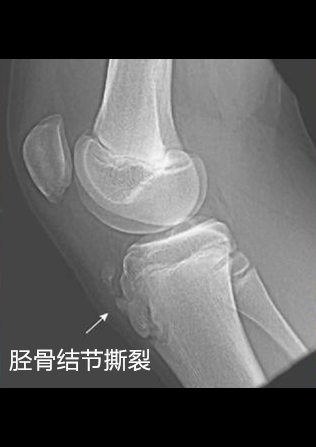

这膝盖下方的区域就是上图红色区域(图示区域4),此区域为髌骨下方,有两个结构:髌韧带及胫骨粗隆,胫骨粗隆又叫胫骨结节。在问及病史及查体以后,我基本可以确定是髌韧带损伤及胫骨结节损伤中的一种了。于是我安排这个小孩去做了一个X线检查。如下图:

从上图X线可以看到胫骨结节撕裂,骨骺增大致密,还可见有碎骨块,结合之前这个小孩描述的的症状及查体,诊断可以明确为:胫骨结节骨软骨病。接下来,我就介绍一下这个胫骨结节骨软骨病,详细告诉大家这究竟是什么病,该怎么治疗?

5. X线可见有胫骨结节骨骺增大、致密或者撕裂等表现。